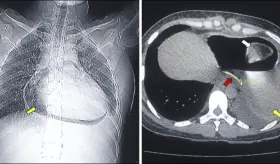

Perforación esofágica por ingestión de espina de pescado genera pericarditis y neumopericardio

Las lesiones causadas por la ingestión de cuerpos extraños son raras pero son un desafío para los servicios de salud por las dificultades en el diagnóstico y manejo.